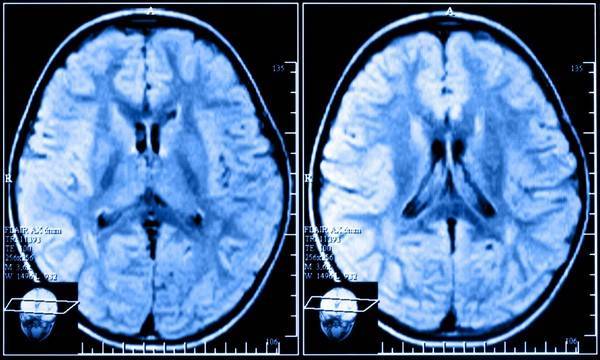

У большинства людей с возрастом появляются очаговые изменения вещества, возникшие из-за дистрофии тканей или вследствие сбоев в кровотоке. Увидеть их можно с помощью магнитно-резонансной томографии (МРТ):

Если человек находится в группе риска, то МРТ ГМ (головного мозга) следует проходить раз в год. В ином случае такое обследование желательно делать раз в 2-3 года для профилактики. Если МРТ покажет высокую эхогенность очага дискуляторного генеза, то это может говорить о наличии онкологического заболевания в головном мозге.

Диагностика начинается с осмотра пациента. контакта с родственниками. Современные аппаратные методы помогают верифицировать диагноз. Применяются:

- магниторезонансная томография (МРТ);

Очаговые поражения головного мозга зачастую протекают бессимптомно. Даже если есть незначительная симптоматика, пациенты редко обращаются к врачам. Выявить патологию трудно. Сделать это можно, пройдя МРТ — исследование. Оно позволяет рассмотреть даже маленькие дегенеративные очаги, способные привести к инсульту или к онкологии.

Врач должен оценить состояние больного, его неврологический статус, а также провести необходимые обследования. Наиболее точные показания дает исследование МРТ, где можно выявить очаги поражения, а также их размеры и локализацию. Томография дает возможность определить изменения плотности ткани мозга даже в начальной стадии заболевания. Правильное прочтение результатов МРТ – важный шаг в начале лечения описываемой проблемы.